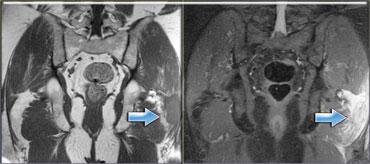

Bên trái cho thấy hình ảnh rách hoàn toàn cơ gân kheo trái tại chỗ nối cơ-gân.

Các gân bị bong tróc và có sự tích tụ dịch.

Bên trái là một bệnh nhân khác cũng bị đứt hoàn toàn gân cơ hamstring.

Có hình thái phù nề ngoại mạc cơ và kích thích thần kinh tọa.

Có thể xảy ra hội chứng hamstring.

Đây là tình trạng đau do sự hình thành sẹo sau chấn thương xung quanh thần kinh tọa (mũi tên).